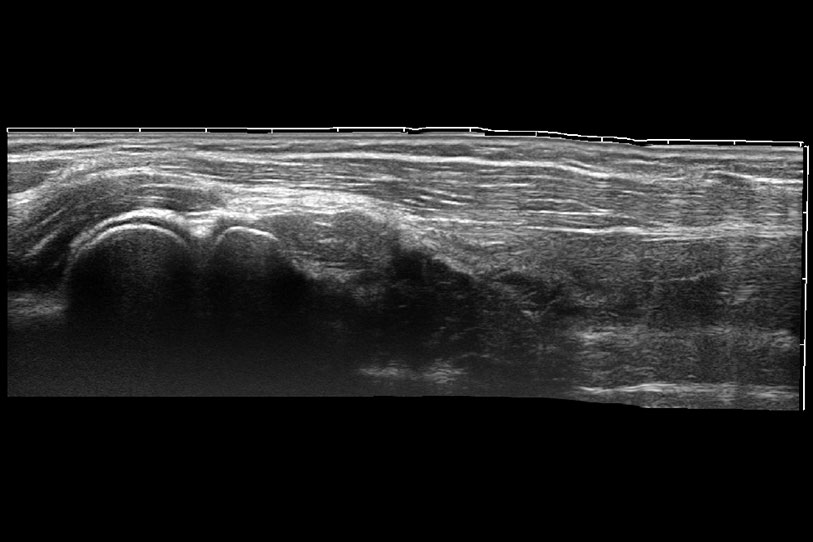

為精細(xì)結(jié)構(gòu)及組織邊緣提供高清晰度的圖像和更大的成像視野。幫助減輕醫(yī)生的用眼疲勞,快速精準(zhǔn)獲得測(cè)量的數(shù)據(jù)。

ProPet 70 進(jìn)一步提升了微米成像算法,更加注重對(duì)基礎(chǔ)原始圖像的還原和保留,在有效減少斑點(diǎn)噪聲、增強(qiáng)組織邊界顯示的同時(shí),避免過度優(yōu)化丟失真實(shí)的解剖信息。